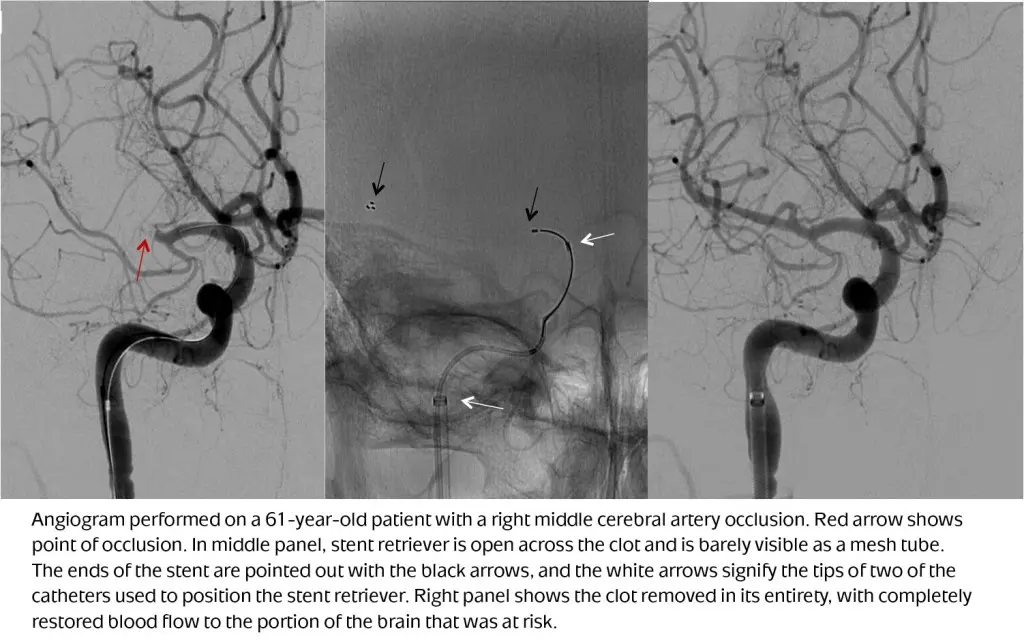

The introduction of a new generation of devices called “stentrievers” is one of the key reasons endovascular clot removal is now proven to be an effective stroke treatment. Similar to the stents used to open clogged arteries in the heart, the stents used to remove clots in the brain are mesh cages that are threaded through the femoral artery up to the blockage. However, unlike those used in the heart, the stents used in stroke treatment do not remain in the body. Instead, they are used to trap and contain the clot, and then are removed.

UVA neurointerventionalists have been performing endovascular thrombectomy procedures for many years, primarily in those ischemic stroke patients unable to receive IV tPA. In light of recent study findings, however, this minimally invasive clot removal procedure will now be the standard of care for ischemic stroke patients with large blockages in a proximal location within the brain, according to Crowley. Endovascular thrombectomy is not recommended for those with clots in the smaller vessels of the brain.